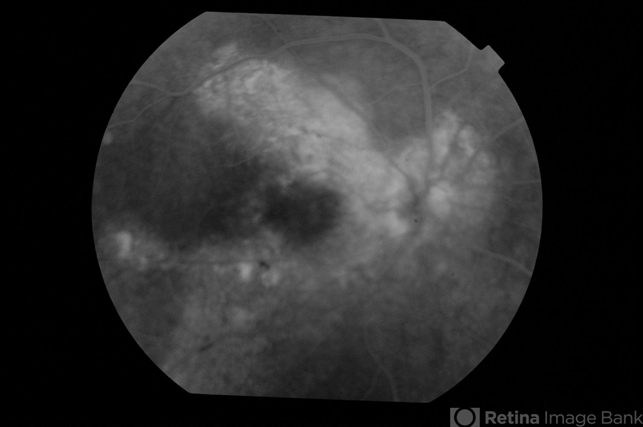

- Chronic CSCR resolution with AntiVEGF

- chronic central serous chorioretinopathy (CSCR)

- Fluorescein of the right eye of a 55-year-old male who presented with symptoms from chronic CSCR (> 3 years) shows extensive RPE window defects and occasional areas of intense hyperfluorescence.